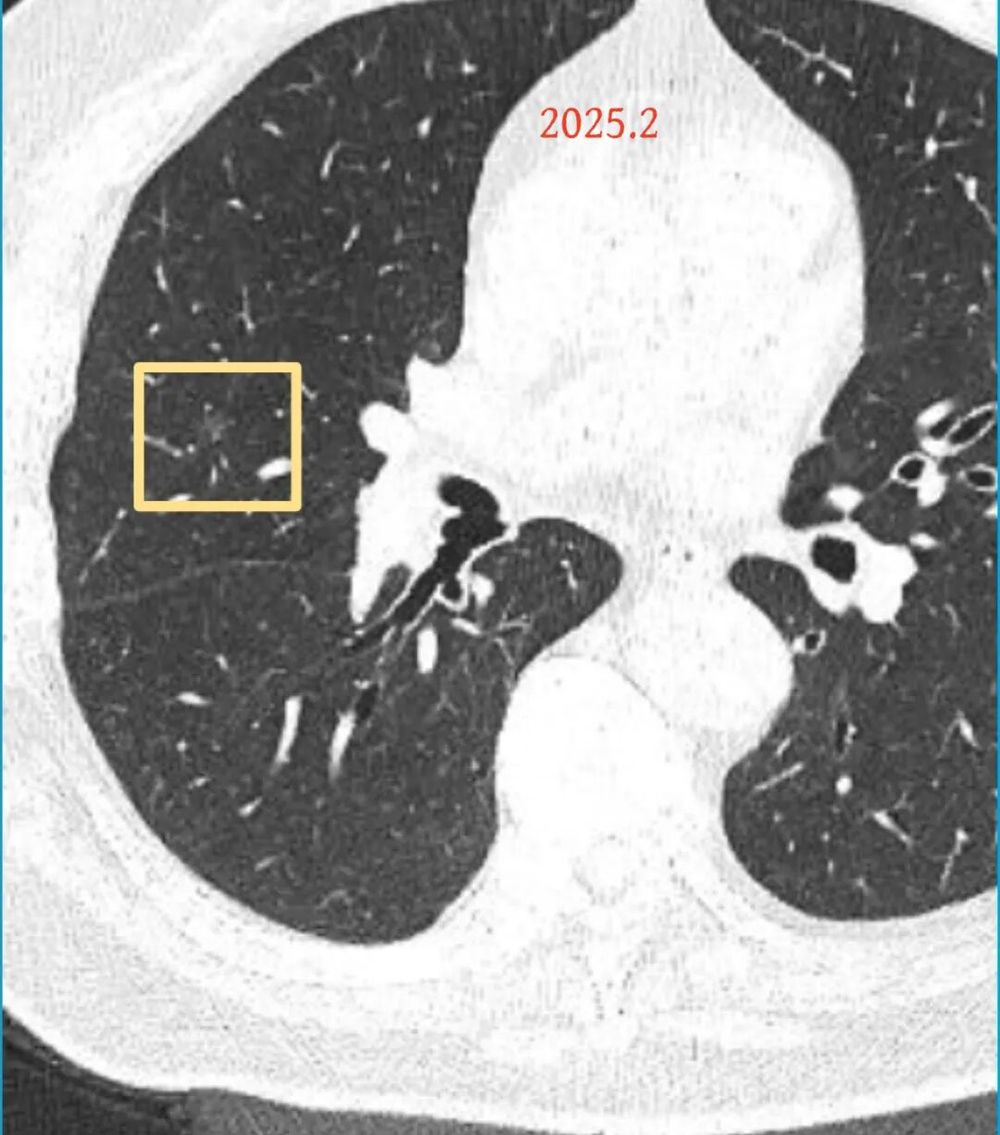

影像展示与分析:

方形的是25年的,红色的主病灶,磨玻璃密度伴少许略偏高点密度,但还说不上典型混合磨玻璃病灶,考虑原位癌或微浸润性腺癌可能性大;蓝色的轮廓与边界欠清,位置靠上叶中央,无法段切或楔切;黄色的多发均淡而纯,分布在两肺。圆形粉色的是主要的两处23年时的样子,对比说不上很明显进展。鉴于若手术得切肺叶,何况两肺他处仍的结节,年纪又74了。我倾向保守点,先6-9个月复查,等进展并风险增加再来考虑怎么办的事。意见供参考!

再看2026年3月最近复查时不同层面病灶A的细节影像特征:

微小血管走向病灶,磨玻璃的密度淡而较纯。